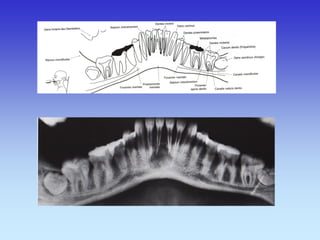

CT- SINUSA TRANSVERZALNI SLOJ

1.Maksilarni sinus

2.Tvrdo nepce

3.Mandibula

4.M. maseter